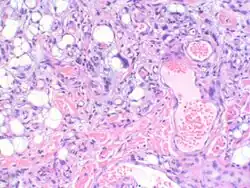

Myxofibrosarcoma-pathology

A histiocytoma is a tumour consisting of histiocytes.[1] Histiocytes are cells that are a part of the mononuclear phagocytic system, a part of the body's immune system that consists of phagocytic cells, which are responsible for engulfing solid particles by the cell membrane to form an internal phagosome by phagocytes and protists.